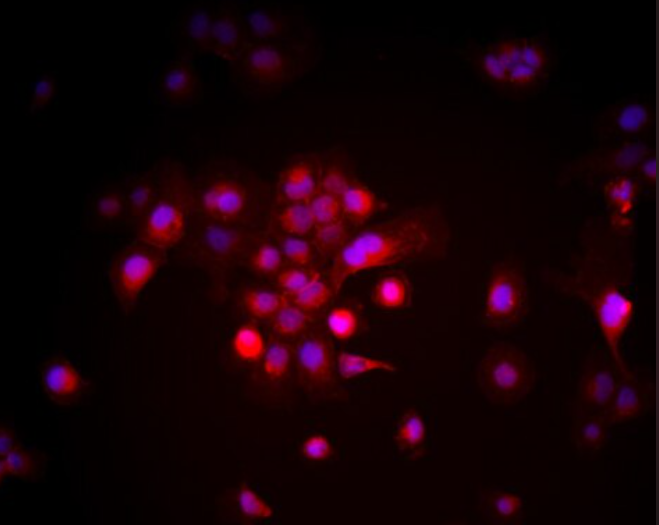

形态特征多角形或不规则,胞质丰富,核仁明显,贴壁生长

高转移人肝癌细胞 MHCC97-H(Human liver cancer cells MHCC97-H)来源于人原发性肝癌患者组织,是在 MHCC97 细胞株基础上通过亚克隆筛选得到的高转移亚株。与其低转移对应株 MHCC97-L 相比,MHCC97-H 细胞具有更强的侵袭和远处转移能力,尤其在裸鼠尾静脉注射模型中,肺转移灶形成明显更频繁。MHCC97-H 细胞为典型上皮样形态,细胞核大、核质比高,贴壁生长紧密,体现出典型肿瘤细胞特性。其生物学行为与临床高转移性肝细胞癌患者高度相似,是研究肝癌转移分子机制、药物靶点发现及体内外实验验证的重要模型。作为广泛应用的高转移人肝癌细胞,MHCC97-H 在肝癌领域相关文献中已有大量报道,且具有良好的模型稳定性与可重复性。

5. 分子标志物检测:通过 Western blot、免疫荧光分析 EMT 相关蛋白(如 E-cadherin、N-cadherin、Vimentin)的变化。